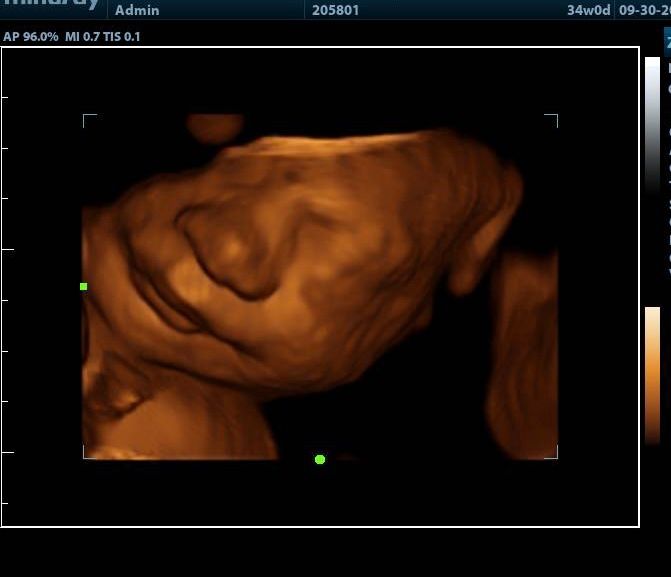

2d, 3d,4d & HD live

Enjoy a private, affordable ultrasound from the comfort of your home, perfect for moms between 7–41 weeks. Share the moment with loved ones by connecting directly to your TV for real-time viewing in 2D, 3D, or 4D. Ideal for baby showers or gender reveal parties!